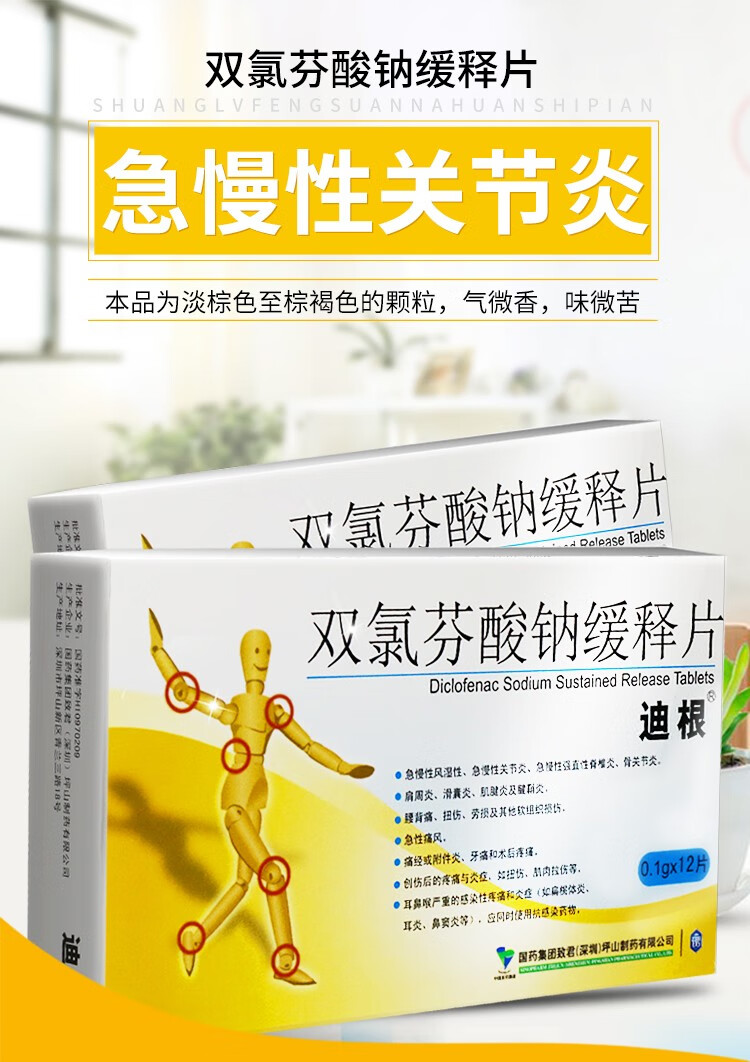

迪根双氯芬酸钠缓释片12片类风湿痛风关节肿痛腰腿疼痛腱鞘炎滑囊炎

迪根双氯芬酸钠缓释片0

1g*12片/盒肌肉疼痛滑囊炎类风湿关节炎痛风急慢性关节炎骨关节炎

迪根 双氯芬酸钠缓释片 0 1g*12片/盒

1g*12片急性痛风骨关节炎急慢风湿性关节炎肩周炎术后疼痛双录分双路